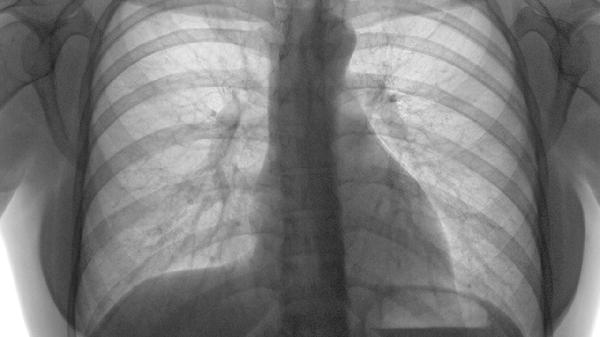

肺积水是一种病理状态,指的是液体在肺部积聚过多,影响到正常的呼吸功能。通常,肺积水会导致胸闷、气促等症状,并且它的形成原因复杂,可能与多种疾病相关。肺积水不仅影响日常呼吸,还可能因为液体压迫肺组织,导致氧气交换障碍,严重时甚至会引起呼吸衰竭,威胁生命。

长期吸烟、饮酒等不良生活习惯会加重肺部疾病的风险。例如,吸烟是慢性阻塞性肺病的主要诱因,而慢性肺病患者可能在病情加重时出现肺积水。如果患有慢性阻塞性肺病或肺癌,患者应定期进行影像学检查,确保肺部没有进一步的积水问题。

针对肺积水,患者应注意休息,避免剧烈运动,保持良好的生活习惯,戒烟限酒。定期进行胸部影像学检查和血液指标检查,及时发现潜在问题并处理,能有效防止病情进一步恶化。如果出现呼吸急促、胸痛等症状,应尽早就医,进行详细检查,明确病因并对症治疗。